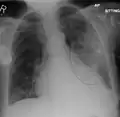

| A chest X-ray showing a very prominent wedge-shape bacterial pneumonia in the right lung | |

The discovery of x-rays made it possible to determine the anatomic type of pneumonia without direct examination of the lungs at autopsy and led to the development of a radiological classification. Early investigators distinguished between typical lobar pneumonia and atypical (e.g. Chlamydophila) or viral pneumonia using the location, distribution, and appearance of the opacities they saw on chest x-rays. Certain x-ray findings can be used to help predict the course of illness, although it is not possible to clearly determine the microbiologic cause of a pneumonia with x-rays alone.